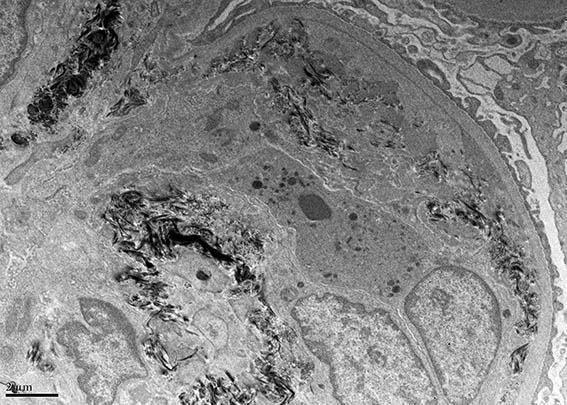

A 33-year-old man presented with pedal edema, persistent proteinuria and hypertension. Her past and family histories were unremarkable. Her blood pressure was 160/100 mm Hg. Physical examination revealed pedal and facial edema, without other alterations. Laboratory tests showed proteinuria of 4.7g/24 h, serum creatinine 1,0 mg/dL, microhematuria, normal serum complement levels, ANA negative; HIV, hepatitis B and C viral infections were negative. Ultrasound of the abdomen showed normal sized kidneys.

Kidney biopsy was performed. Look at the images.

Figure 6. Electron microscopy, original magnification, X4,000.